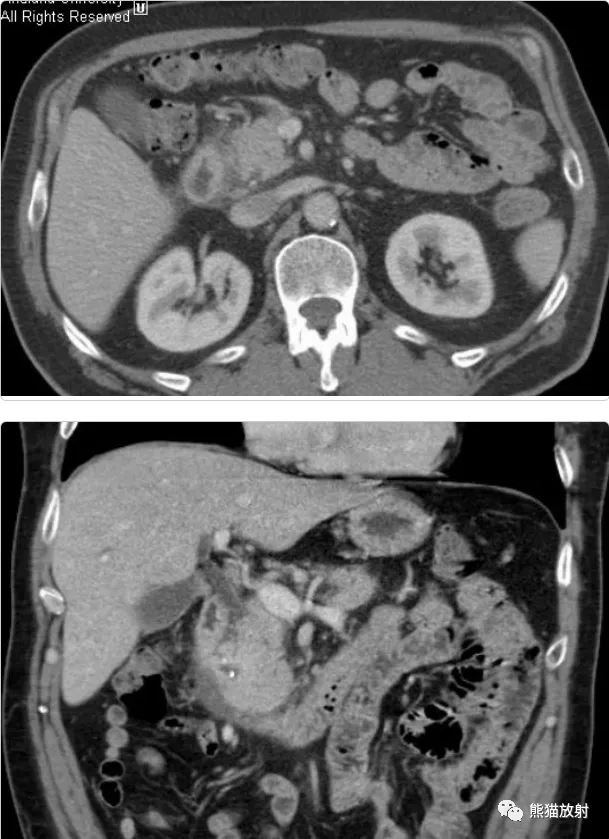

男 , 60岁 , 腹痛、乏力、体重减轻 。 CA19-9正常 。

行上腹部CT增强(动脉期、实质期、冠状MPR)

影像表现:

- 胰头略饱满 , 胰腺实质密度尚均匀;

- 胰十二指肠沟区域间隙浑浊 , 可见等低密度灶 , 不均质轻中度强化;

- 邻近十二指肠壁略增厚 , 强化较明显;

- 主胰管无扩张 , 胆总管略窄;

- 周围未见明显肿大淋巴结 。